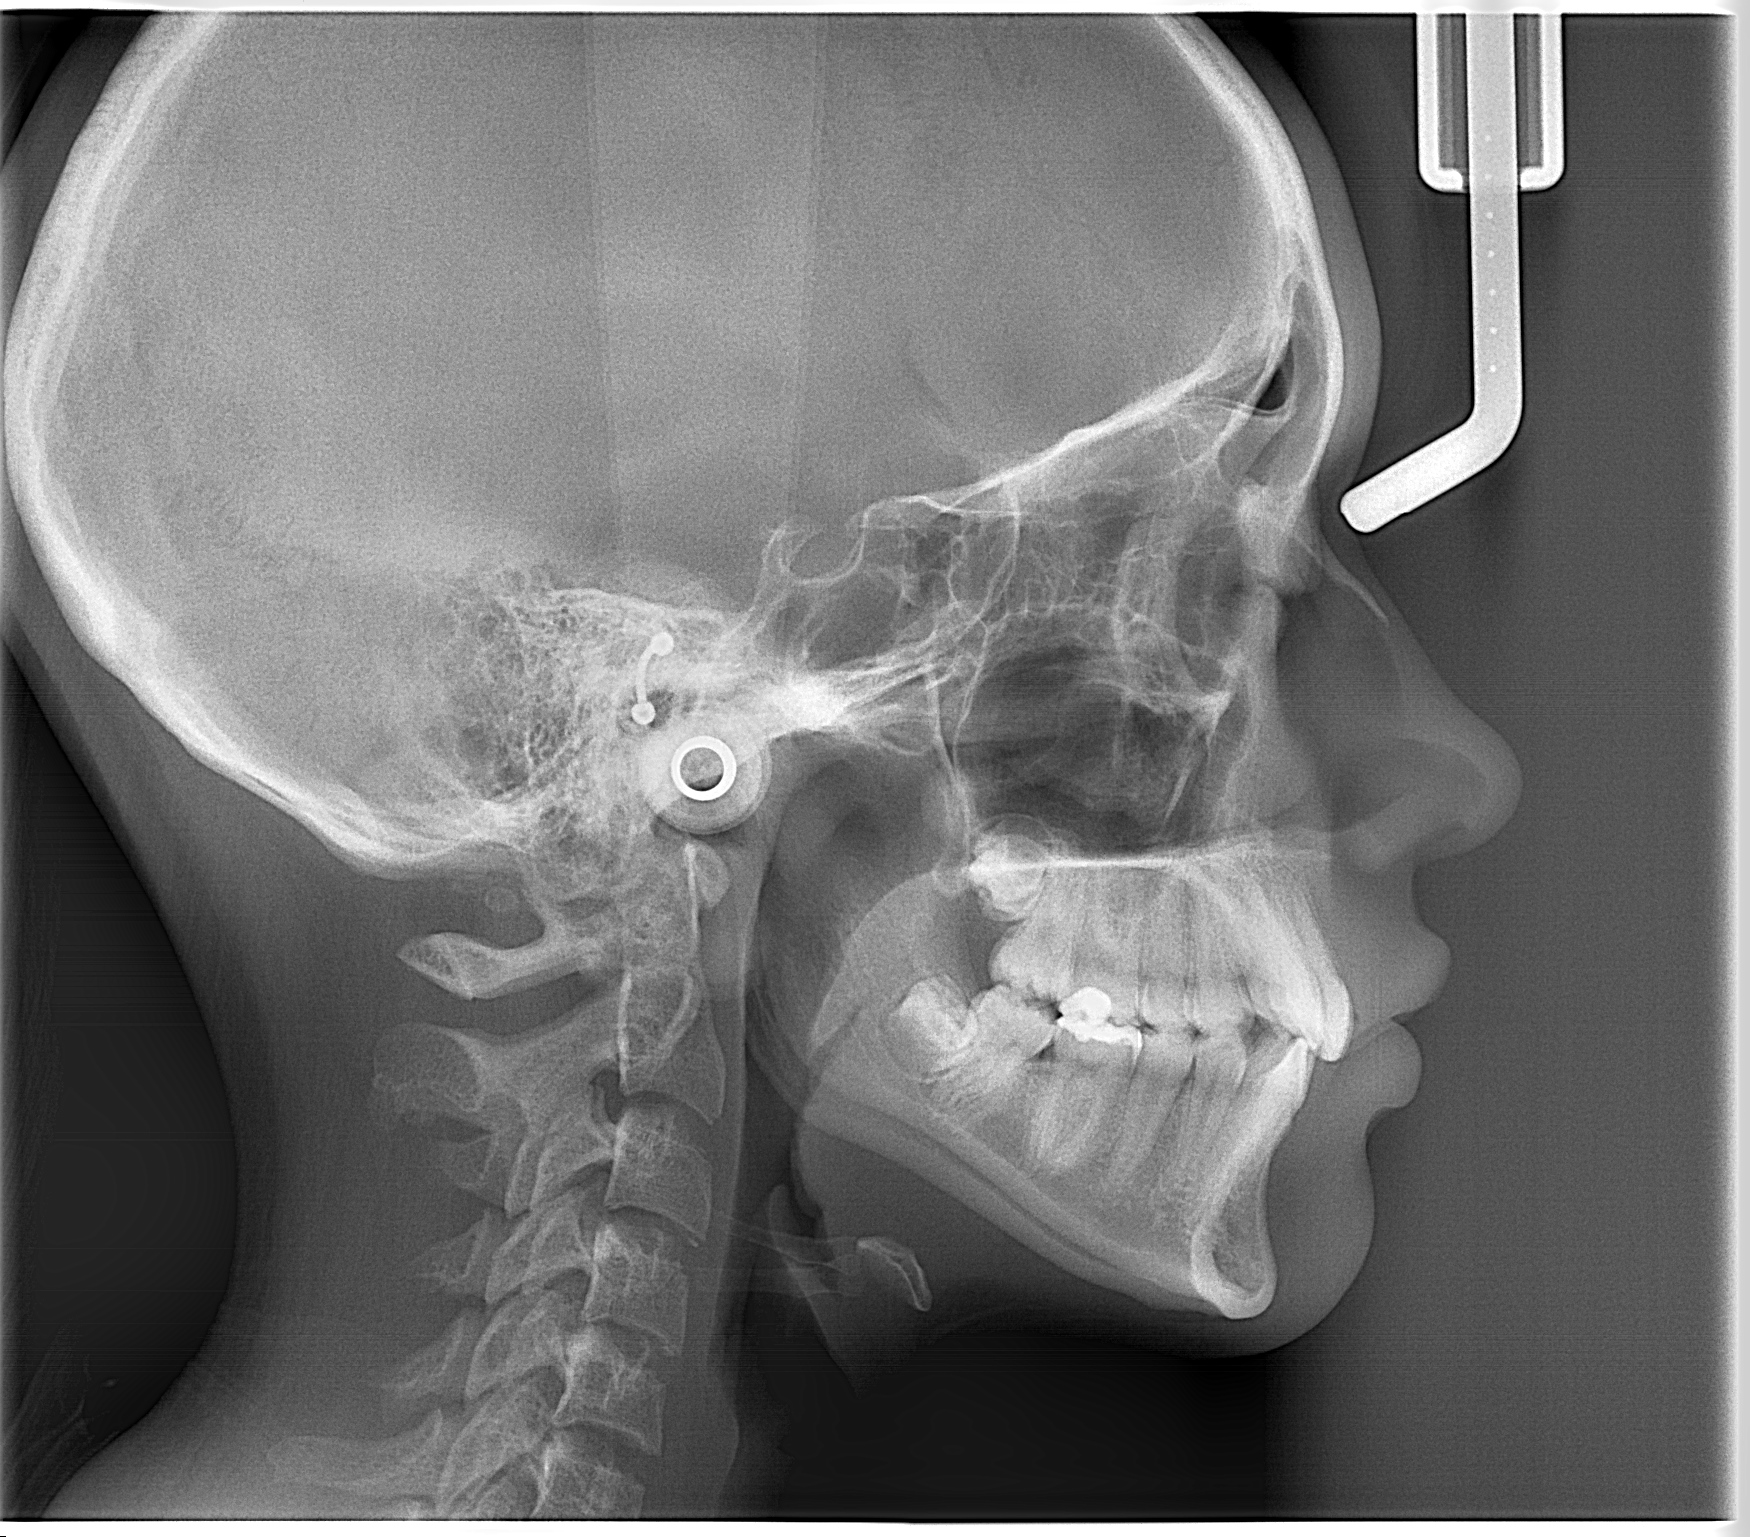

- Radiografía cefálica lateral: Radiografía extraoral que permite evaluar permeabilidad de vía área, ver el tamaño y posición de los maxilares, permite identificar la relación intermaxilar, entre otros.

Esta radiografía ayuda a evaluar la permeabilidad de vías aéreas, el tamaño y posición de los maxilares, y la relación intermaxilar.